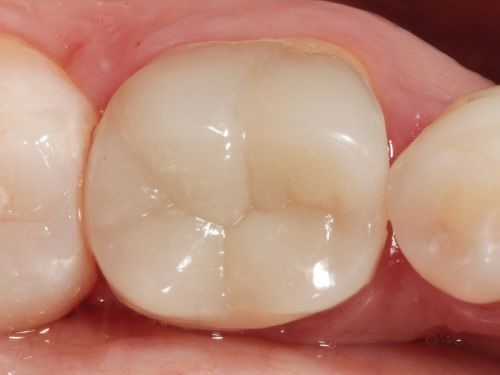

A 35-year-old male presented to the clinic to replace some inadequate restorations, one of which was for the lower right first molar (Fig. 1). For this tooth, the molar was restored with composite resin using the direct technique. The operative field was isolated, the old restoration was removed, and surface hybridization was completed using Futurabond U universal adhesive from Voco (Fig. 2). After placing a sectional matrix and a spacer ring, the composite resin (Voco’s GrandioSO 4U, shade A2) was placed in the proximal box with a thickness less than 4 mm, which is the maximum recommended thickness for the chosen material (Fig. 3). Additional increments of composite resin were applied to complete the anatomical stratification. The final morphology was sculpted, followed by light-curing to ensure complete polymerization (Fig. 4). The rubber dam was removed (Fig. 5), and the occlusion was adjusted using a finishing carbide bur with 12 blades (Fig. 6). Finishing and polishing was completed, with the final result shown in the Figures 7 and 8.